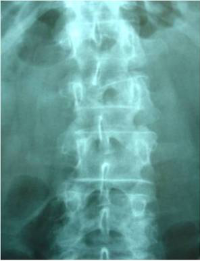

Estabilització percutània de fractures vertebrals inestables

En casos de fractures vertebrals complexes, inestables, comminutes, etc. es requereix una estabilització addicional de la fractura mitjançant una artròdesi percutània, i en alguns casos en els quals hi ha compromís neurològic, una descompressió del canal medul·lar. L’artrodesi percutània permet estabilitzar l’estructura compromesa de la columna vertebral i descarregar la càrrega del pacient sobre la fractura. Addicionalment se solen cementar les vertebres artròdesis i la fractura vertebral mitjançant cifoplastia.

Fractura Vertebral Ejemplo de Caso Clínico